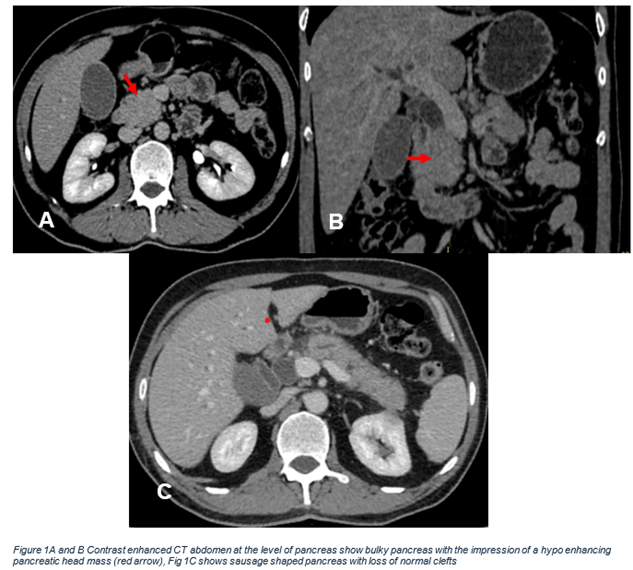

We report the case of a 50-year-old male who presented with left flank pain, jaundice, and significant weight loss over the past three months. His medical history included diabetes and a recent endoscopic retrograde cholangiopancreatography (ERCP) for a distal common bile duct (CBD) stricture with plastic stent placement. Physical examination was mostly unremarkable except for jaundice. Initial lab results showed normal complete blood count (CBC) and urea & electrolytes (U&E). Liver function tests (LFTs) were abnormal, with an obstructive pattern (ALT 121 U/L, AST 116 U/L, GGT 32 U/L, total bilirubin 6.26 mg/dL, alkaline phosphatase 285 U/L). CA19-9 was also elevated. A CT scan revealed a 34 mm x 28 mm mass in the head of the pancreas with a CBD stent in place. (Figure 1).

Figure 1A and B: Contrast enhanced CT abdomen at the level of pancreas show bulky pancreas with the impression of a hypo enhancing pancreatic head mass (red arrow),

Figure 1C: Shows sausage shaped pancreas with loss of normal clefts.